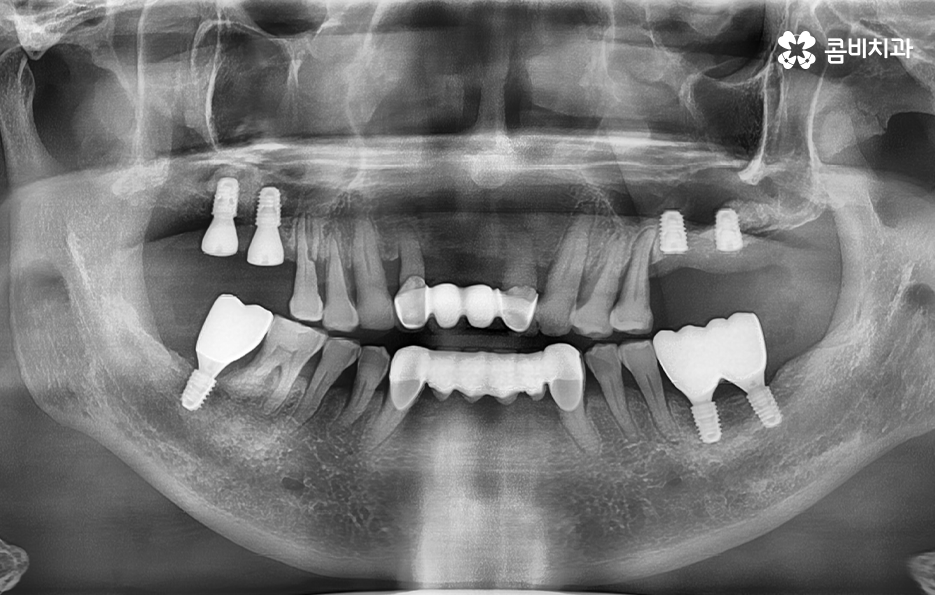

50대에 관리가 잘 안되던 치주질환은 결국 60대에 이르러 한꺼번에 여러 치아를 상실하게 되고 그에 따라 임플란트도 여러개를 식립해야 하는 사례가 많다는 점을 주목하실 필요가 있는데요

50대에는 치주염, 충치, 외상과 같은 사유로 인해 치아를 하나 둘씩 잃게 되는 사례가 많으며 치아 상실 후에 즉시 임플란트 치료를 받지 않는다면 잇몸과 턱뼈는 서서히 퇴축되고 약화되며 치열이 망가질 수 있는 우려와 교합이 제대로 물리지 않는 불균형이 나타날 수 있어요

50대는 앞으로의 기대수명이 길기 때문에 치아 상실 후 방치하기 보다는 꼭 임플란트 치료를 하는 것이 합리적이며 치아 상실 후에는 골 흡수가 진행되지만 임플란트를 하면 잇몸 뼈를 보존할 수 있다는 점에서도 앞으로의 노후대비에 있어서도 임플란트는 중요한 시술이 될 수 있어요